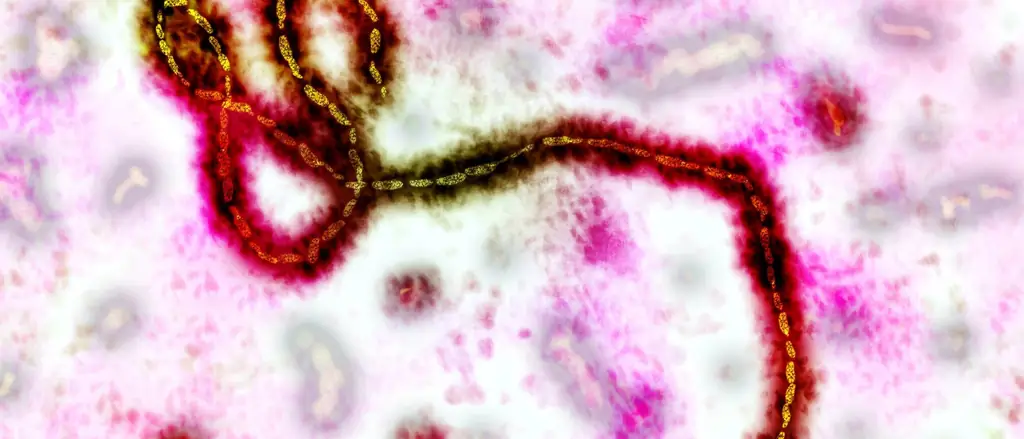

Тысячи участников испытаний, две вакцины-кандидаты, одно плацебо: крупнейшее на сегодняшний день исследование Эболы началось в Либерии. Франциска Баденшир взяла интервью у руководителя исследования Стивена Б. Кеннеди.